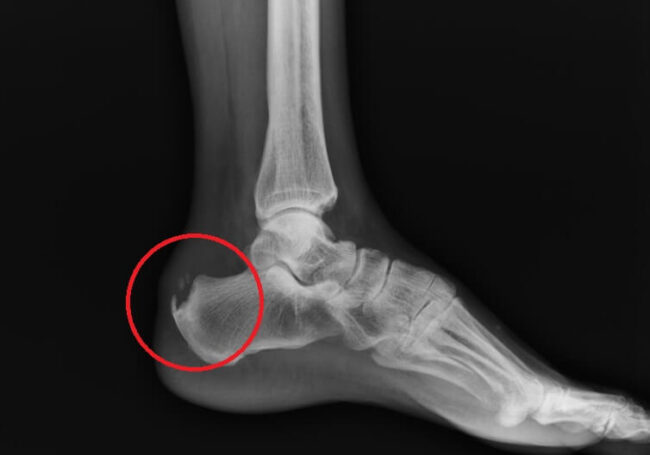

Костяные наросты могут возникать не только на шее, но и других частях тела

Несмотря на все это, факт остается фактом, и у некоторых людей действительно есть отростки. Вы можете попробовать нащупать их у себя — наклоните голову вперед и приложите руку к нижней части черепа. Если что-то выросло, вы наверняка узнаете об этом наощупь. Ученые знают об этих образованиях уже давно, их упоминания можно найти даже в документах XVIII века. Обычно выступы на костях служат для того, чтобы к ним крепились мышцы. Из-за высокой нагрузки мышцы пребывают в напряжении, что и может провоцировать появление «рогов». Вырастание аномальных костных структур в медицине называется энтезофитом и, в большинстве случаев, они никак не влияют на качество жизни. Но иногда они врастают в мышцы, и это уже хоть и редкое, но довольно опасное явление.

Результаты научной работы были опубликованы в журнале из-за того, что модераторы не смогли своевременно проверить их на достоверность. Архив Scientific Reports является очень популярным и ежедневно там публикуются десятки или даже сотни текстов. Поэтому авторам проекта просто не хватает времени сразу же их проверять. В ходе недавнего рассмотрения работы о взаимосвязи использования смартфонов с возникновением «рогов» на шее, модераторы обнаружили очень важную деталь. В проведенном исследовании было изучено 1200 рентгеновских снимков пациентов из австралийского Квинсленда в возрасте от 18 до 86 лет. Необычные наросты были найдены в телах 33% людей. При проведении работы использованы материалы из клинической базы, а для чистоты результатов лучше использовать случайно отобранных добровольцев.